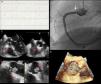

We report the case of a 65-year-old woman admitted to the emergency department with constricting chest pain of one hour's duration. The pre-hospital electrocardiogram (ECG) showed ST-segment elevation in the inferior leads (Figure 1A). On admission the patient was asymptomatic and the ECG alterations had resolved. Intermittent periods of ST-segment elevation were observed on telemetry while the patient was being prepared for urgent catheterization, which revealed interruption of contrast in the ostium of the right coronary artery, causing elevated intracoronary gradients during selective angiography (Figure 1B). This was initially thought to represent dissection and two stents were implanted, but an echocardiogram on the same day completely changed our view of the case: transesophageal echocardiography performed for a more accurate characterization showed akinesia of the inferior wall and a mobile structure, 1.4cm×0.9cm, pedunculated, between the right coronary sinus and the non-coronary sinus, which did not impede valve function, but intermittently partially obstructed the stent (Figure 1C–E). On magnetic resonance imaging, this structure revealed gadolinium enhancement. A few days later the mass was excised and histological study showed it to be a cardiac papillary fibroelastoma, which had been one of the possible diagnoses postulated during the investigation.

Diagnostic exams performed during the investigation of this case: (A) initial electrocardiogram showing ST-segment elevation in the inferior leads; (B) right coronary angiography showing interruption of contrast (arrow) in the ostium; (C and D) transesophageal echocardiogram of the tumor (dashed arrow) showing its location and relation to the stent (solid arrow) in the right coronary artery; (E) three-dimensional transesophageal echocardiogram of the tumor (dashed arrow).